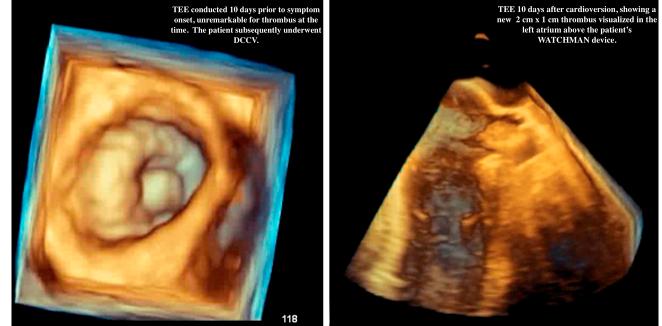

A 66-year-old male with a history of atrial fibrillation (AF) and a left atrial appendage occlusion (LAAO) device, compliant with apixaban, presented with dyspnea and lightheadedness. He was cardioverted into sinus rhythm, 10 days before symptom onset, with TEE unremarkable at the time. An ECG revealed that the patient converted back into AF and a repeat cardioversion was scheduled. At the patient's request, a TEE was obtained, revealing a new 2 cm×1 cm thrombus in the left atrium above the WATCHMAN device. Cardioversion was canceled and the patient was hospitalized for AF management.

一名66岁男性,有房颤(AF)病史且植入了左心耳封堵(LAAO)装置,服用阿哌沙班,出现呼吸困难和头晕。症状出现前10天,他被转复为窦性心律,当时TEE检查未见异常。心电图显示患者又转为房颤,计划进行重复心脏复律。应患者要求,进行了TEE检查,结果显示在WATCHMAN装置上方的左心房有一个新的2cm×1cm血栓。心脏复律取消,患者因房颤管理住院。